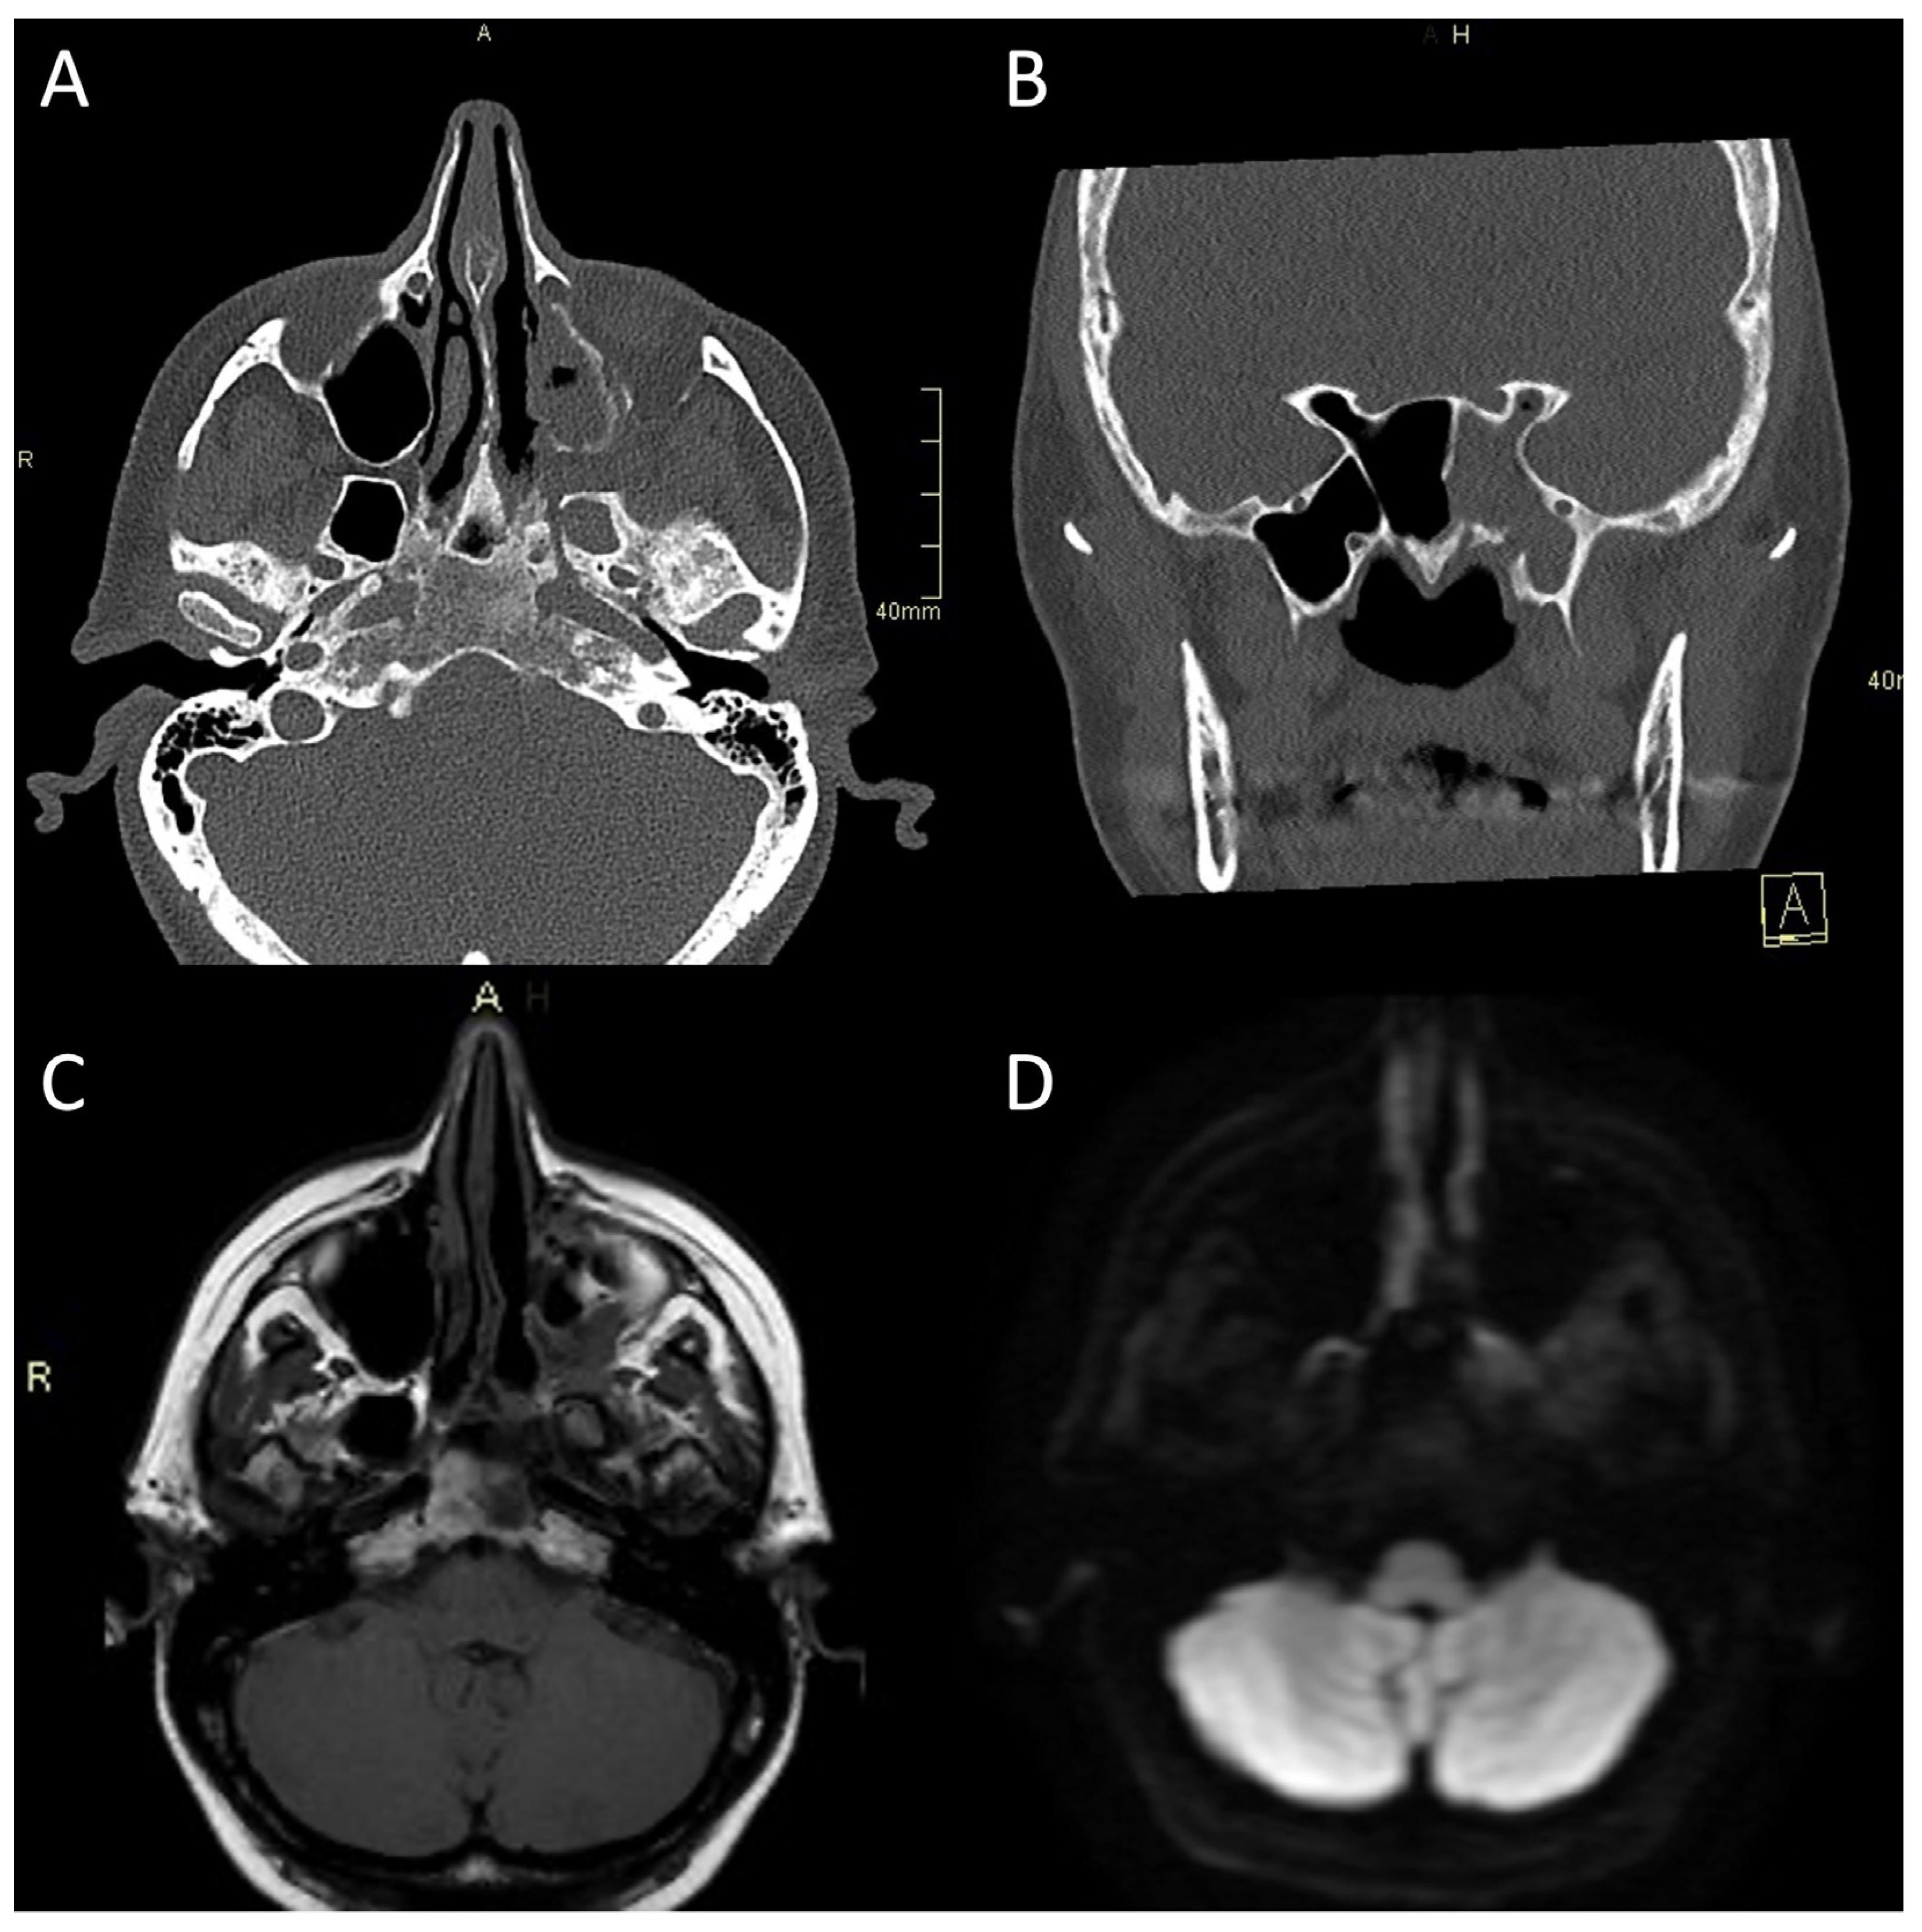

4.1.1. CT Imaging

4.1.2. MR Imaging

- Mejzlik, J.; Cerny, M.; Zeinerova, L.; Dedkova, J.; Kopriva, J.; Zadrobilek, K.; Adamkov, J.; Chrobok, V.; Pellantova, V. The Routes of Infection Spread in Central Skull-Base Osteomyelitis and the Diagnostic Role of CT and MRI Scans. BMC Med. Imaging 2019, 19, 60. [Google Scholar] [CrossRef] [PubMed]